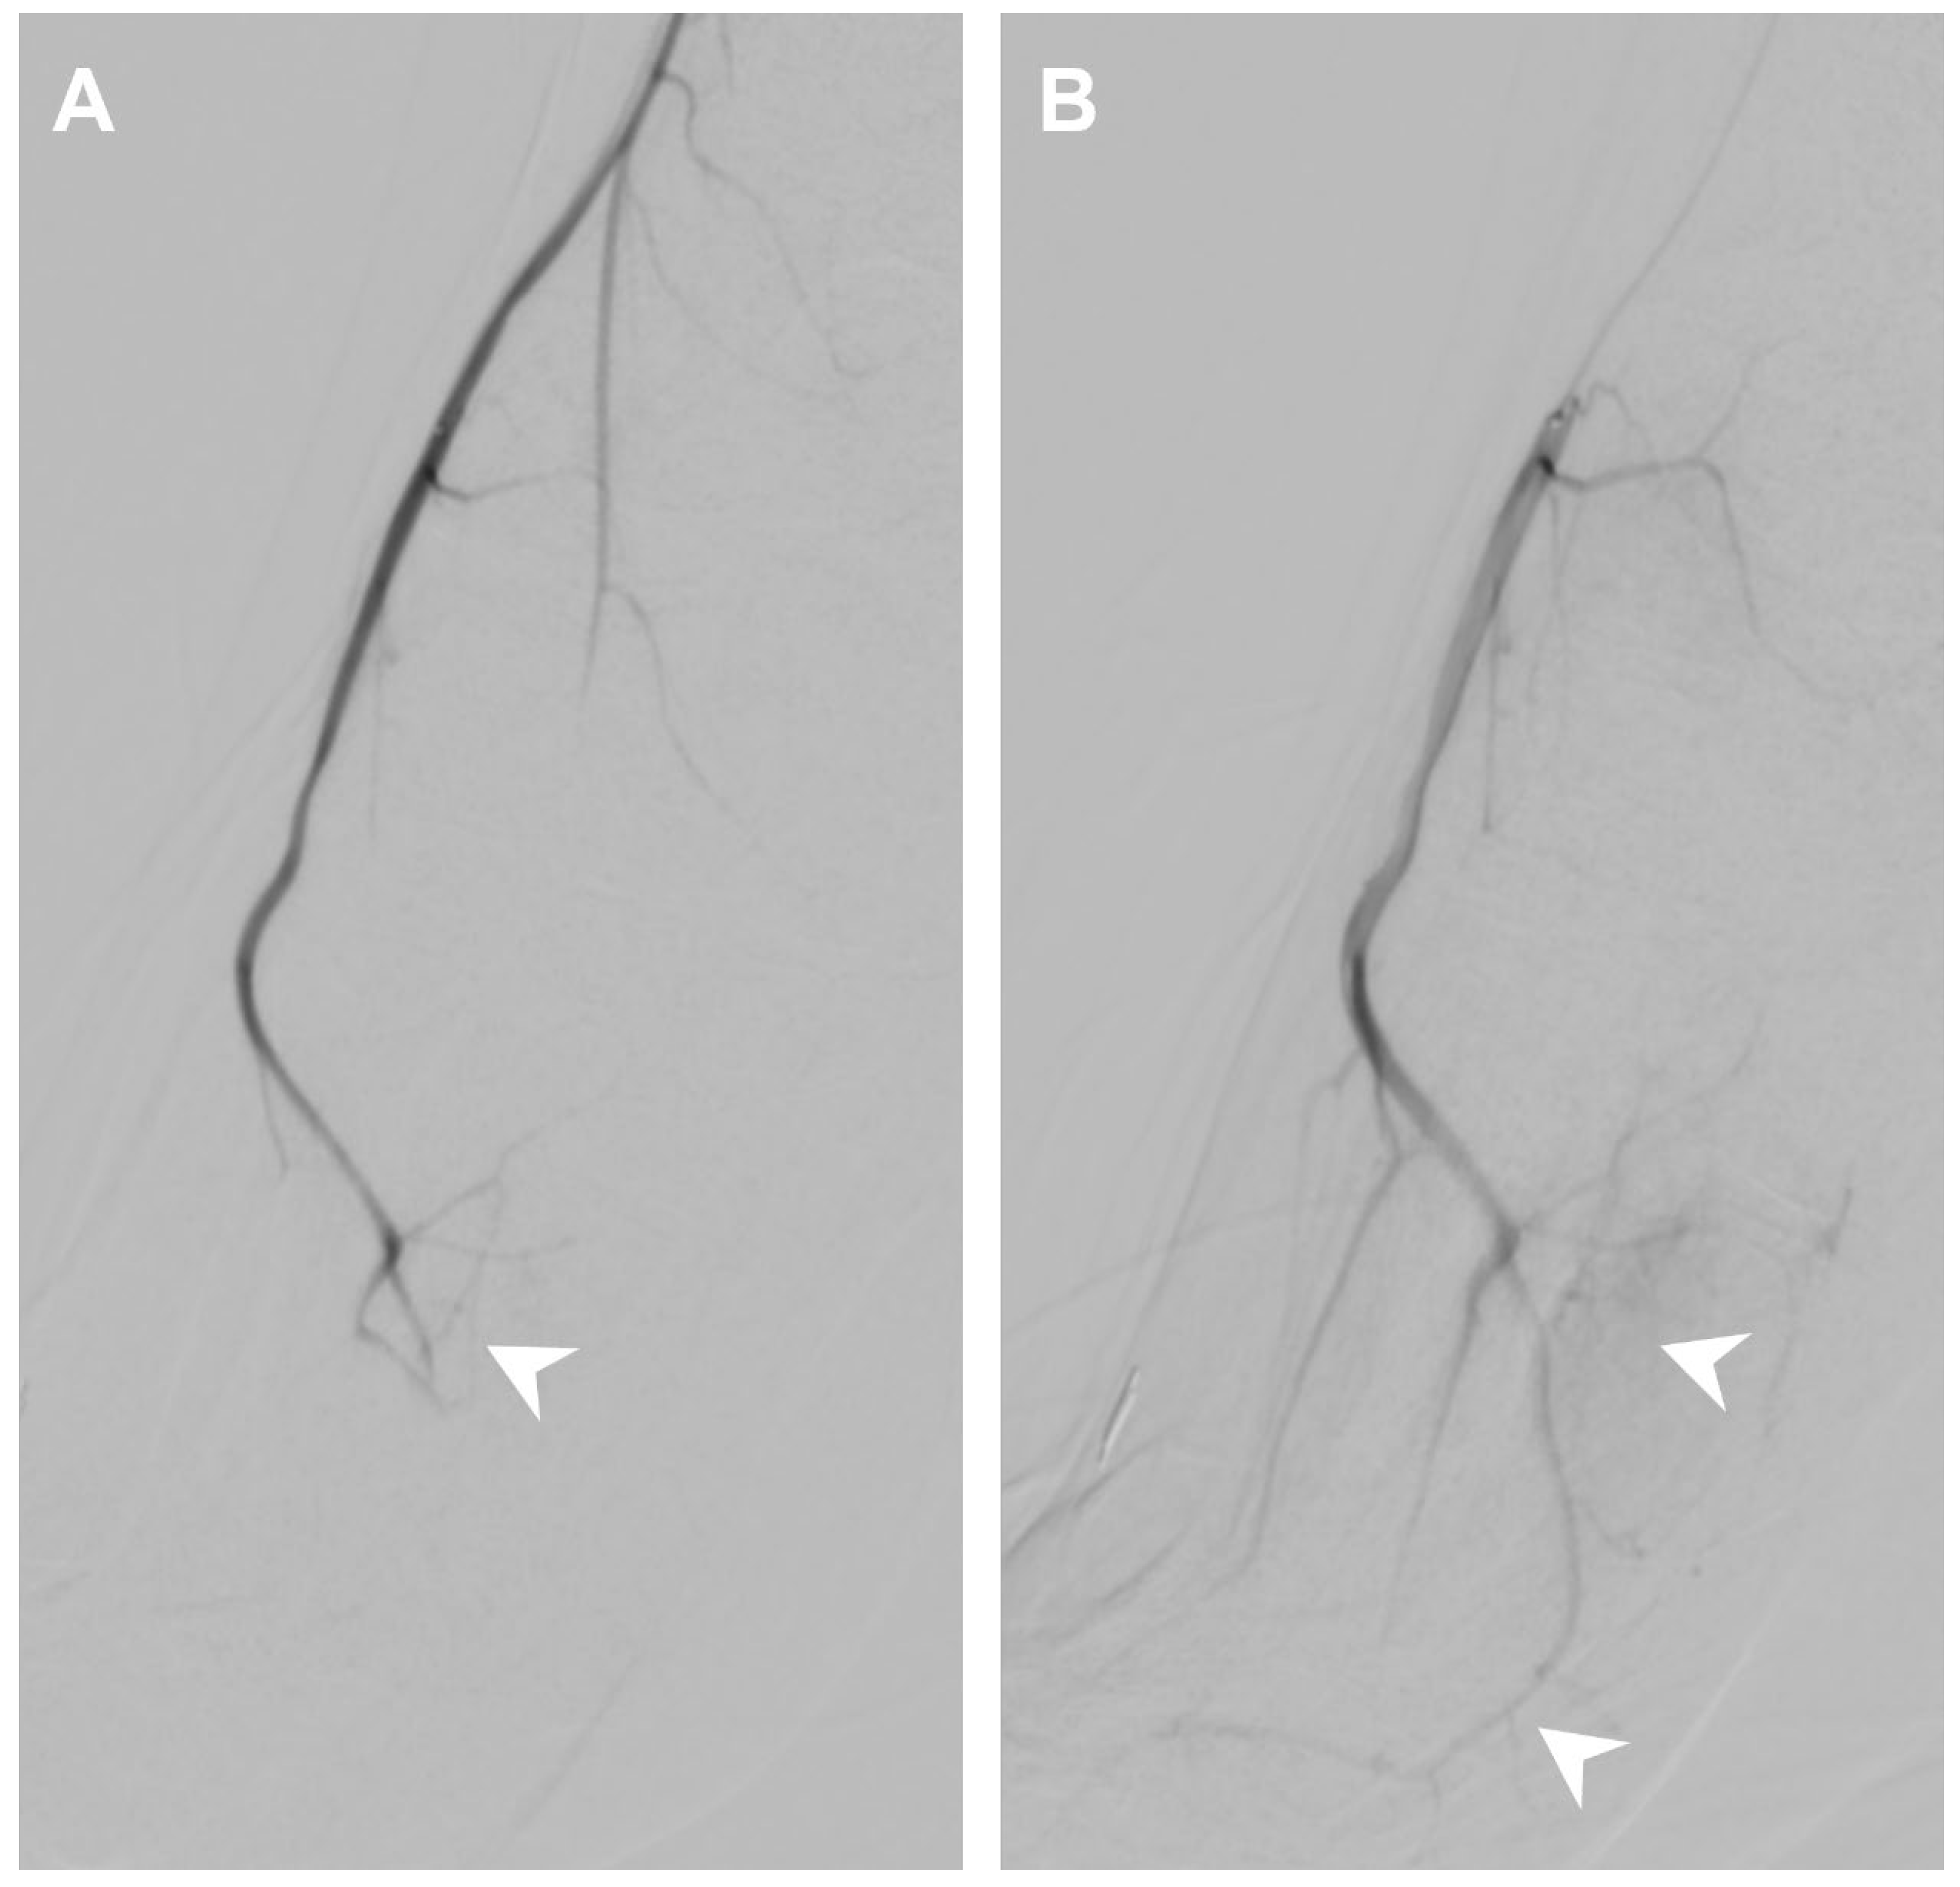

3.4. Patellar Tendinopathy

| Patellar tendinopathy | Lateral inferior genicular artery | 0.85 | 1.03 |